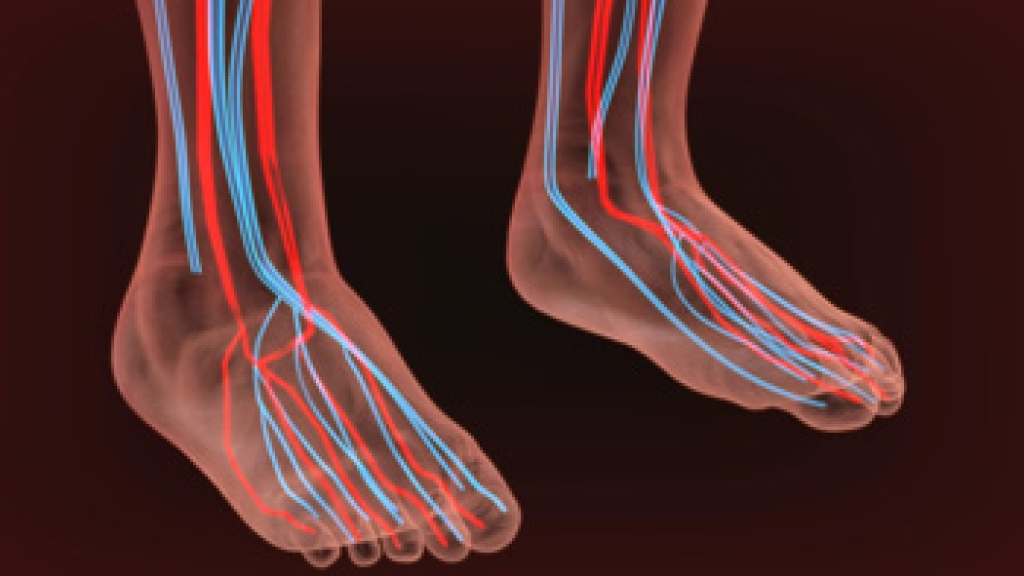

Cuboid syndrome is a common cause of lateral foot pain, which is pain on the outside of the foot. The condition may happen suddenly due to an ankle sprain, or it may develop slowly overtime from repetitive tension through the bone and surrounding structures.

A common symptom of cuboid syndrome is pain along the outside of the foot which can be felt in the ankle and toes. This pain may create walking difficulties and may cause those with the condition to walk with a limp.